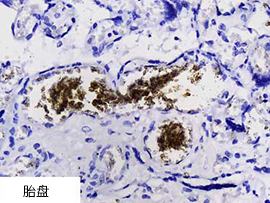

"使用其他品牌探针和Enzo AMPIVIEW™ 探针通过ISH检测了一些正常的大脑和胎盘作为SARS-CoV-2 RNA的阴性对照。对比竞品探针的背景(红细胞),使用Enzo探针的背景低。" ——Dr. Nuovo, 俄亥俄州立大学 |